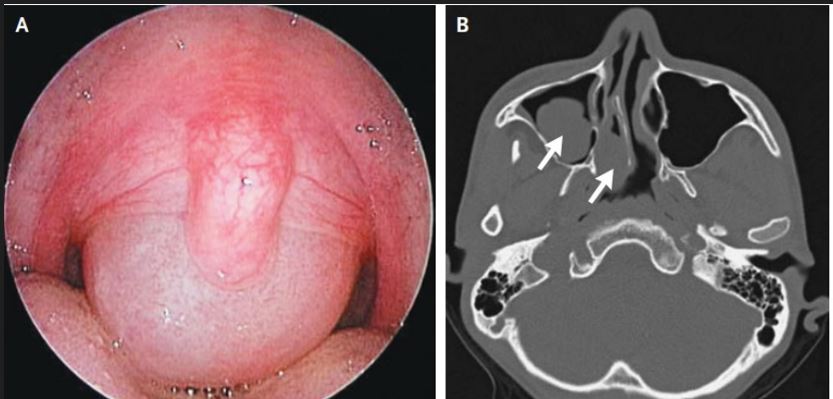

Introduction: Antrochoanal polyps (ACPs) are benign growths originating from the maxillary sinus and extending into the nasal cavity. This article delves into their etiology, pathophysiology, diagnosis, treatment modalities, and preventive measures.<br />Etiology: The exact cause of ACPs remains elusive, but chronic inflammation in the paranasal sinuses is a prominent factor. Allergies, recurrent infections, or anatomical variations in sinus structures may contribute to their development.<br />Pathophysiology: ACPs typically arise from the mucosal lining of the maxillary sinus. As chronic inflammation persists, a polypoid mass forms, gradually extending through the sinus ostium into the nasal cavity. Their growth may obstruct normal sinus drainage, leading to further inflammation and expansion.<br />Diagnosis:<br />1. Clinical Assessment: Patients often present with nasal obstruction, facial pain, and anosmia.<br />2. Endoscopic Examination: Direct visualization through nasal endoscopy aids in confirming the presence, location, and extent of the polyps.<br />3. Imaging Studies: CT scans provide detailed images, helping clinicians evaluate the size and characteristics of the polyps and their impact on surrounding structures.<br />Treatment:<br />1. Medical Management: Corticosteroids, either systemic or topical, are effective in reducing inflammation and shrinking polyps.<br />2. Surgical Intervention: Endoscopic sinus surgery is the primary treatment for ACPs, aiming to remove the polyps and restore normal sinus function.<br />3. Adjuvant Therapies: Allergen immunotherapy or antibiotics may be considered based on underlying causes, such as allergies or infections.<br />Prevention:<br />1. Allergy Management: Identifying and managing allergies can prevent recurrent inflammation, a potential trigger for ACPs.<br />2. Prompt Treatment of Sinusitis: Timely intervention for sinus infections reduces the risk of chronic inflammation leading to polyp formation.<br />3. Regular Follow-ups: Patients with a history of ACPs should undergo regular check-ups to monitor for recurrence and address any developing issues promptly.<br />Conclusion: Antrochoanal polyps, though benign, can significantly impact a patient's quality of life. A comprehensive understanding of their etiology, pathophysiology, early diagnosis, and appropriate treatment is crucial. By integrating preventive measures, clinicians can enhance patient outcomes and minimize the risk of recurrence.